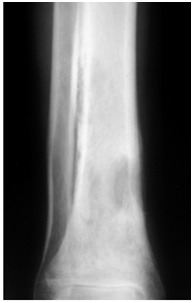

Differential diagnosis: Ewing sarcoma, aggressive neoplasm or Stress fracture (Figure 10).

Figure 10 Plain x-ray of the ankle in a case of osteomyelitis showing permeative osteolysis.